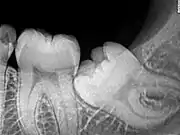

Wisdom teeth likely become impacted because of a mismatch between the size of the teeth and the size of the jaw. Impacted wisdom teeth are classified by their direction of impaction, their depth compared to the biting surface of adjacent teeth and the amount of the tooth's crown that extends through gum tissue or bone. Impacted wisdom teeth can also be classified by the presence or absence of symptoms and disease. Screening for the presence of wisdom teeth often begins in late adolescence when a partially developed tooth may become impacted. Screening commonly includes clinical examination as well as x-rays such as panoramic radiographs.

Impacted wisdom teeth are classified by the direction and depth of impaction, the amount of available space for tooth eruption, and the amount of soft tissue or bone (or both) that covers them. The classification structure helps clinicians estimate the risks for impaction, infections and complications associated with wisdom teeth removal.[6] Wisdom teeth are also classified by the presence (or absence) of symptoms and disease.[7]

One review found that 11% of wisdom teeth will have evidence of disease and are symptomatic, 0.6% will be symptomatic but have no disease, 51% will be asymptomatic but have disease present and 37% will be asymptomatic and have no disease.[7] Impacted wisdom teeth are often described by the direction of their impaction (forward tilting, or mesioangular being the most common), the depth of impaction and the age of the patient as well as other factors such as pre-existing infection or the presence of pathology (cysts, tumors or other disease).[5]:143–144 Each of these factors is used to predict the difficulty (and rate of complications) when removing an impacted tooth, with age being the most reliable predictor[8] rather than the orientation of the impaction.[9]

The diagnosis of impaction can be made clinically if enough of the wisdom tooth is visible to determine its angulation, depth, and if the patient is old enough that further eruption or uprighting is unlikely. Wisdom teeth continue to move to the age of 25 years old due to eruption, and then continue some later movement owing to periodontal disease.[18]

If the tooth cannot be assessed with clinical exam alone, the diagnosis is made using either a panoramic radiograph or cone-beam CT. Where unerupted wisdom teeth still have eruption potential several predictors are used to determine the chance of the teeth becoming impacted. The ratio of space between the tooth crown length and the amount of space available, the angle of the teeth compared to the other teeth are the two most commonly used predictors, with the space ratio being the most accurate. Despite the capacity for movement into early adulthood, the likelihood that the tooth will become impacted can be predicted when the ratio of space available to the length of the crown of the tooth is under 1.[5]:141